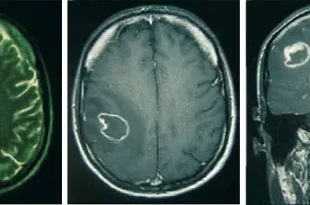

Hochgeschwindigkeitsstanze (Jetbiopsie) Nach lokaler Betäubung wird eine kleine Biopsienadel unter Ultraschallkontrolle an den zu untersuchenden Bezirk herangeführt, um dann mittels Hochgeschwindigkeit geringe Mengen aus dem Tumor zu entnehmen. Diese Methode wird in der Regel zur …